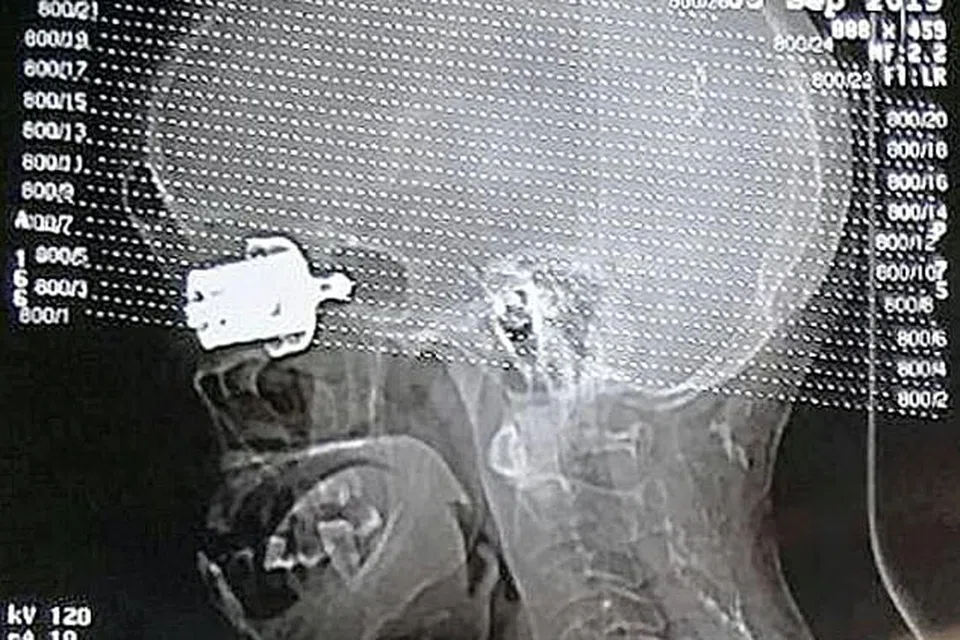

மருத்துவமனைக்குச் சென்றபோது அவரது முகத்தில் குக்கர் வெயிட்டை காண முடியவில்லை. பின்னர் 'ஸ்கேன்' செய்தபோது அது முழுவதுமாக உள்ளிறங்கி மூளைக்கு அருகில் இருப்பது கண்டுபிடிக்கப்பட்டது. இதையடுத்து மருத்துவர்கள் அந்த வெயிட்டை பெண்ணின் தலையில் இருந்து அறுவை சிகிச்சை மூலம் வெளியே எடுத்தனர். எனினும் அந்தப் பெண்ணின் இடது கண் பார்வை பறிபோனது.